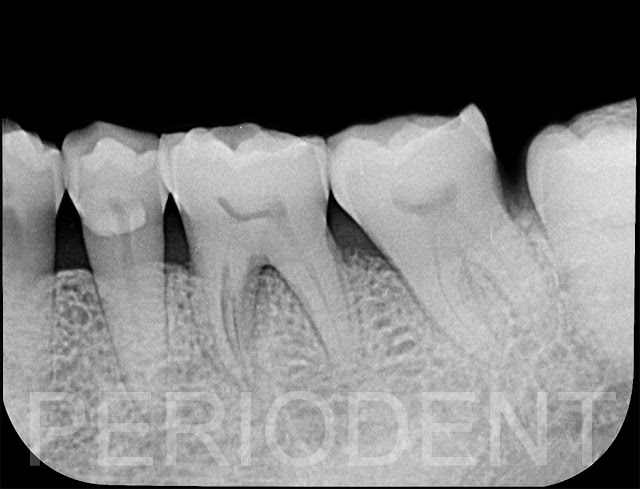

患者左下第一大臼齒有Gumboil,從x光片檢查顯示牙根縱裂